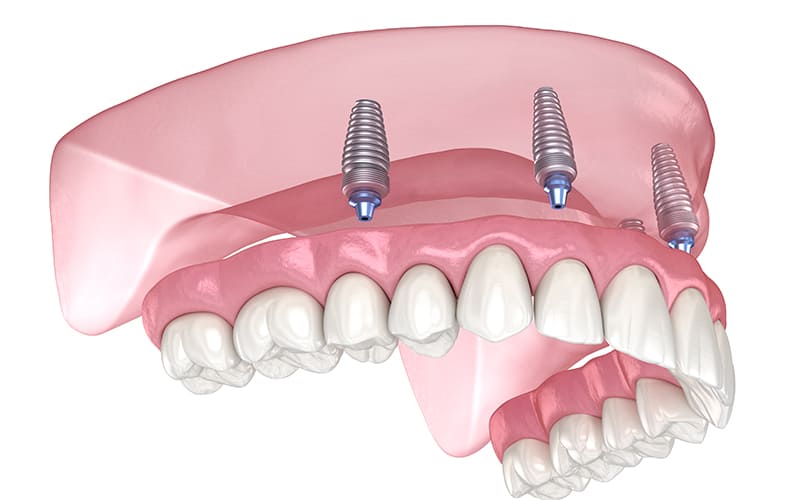

インプラントオーバーデンチャー

インプラントを数本埋め込み、その上に入れ歯を固定する方法です。

メリット

- 入れ歯のズレや外れを防ぐ

- しっかりと噛めるため、食事を楽しめる

- 口蓋を覆わない設計も可能で、違和感が少ない